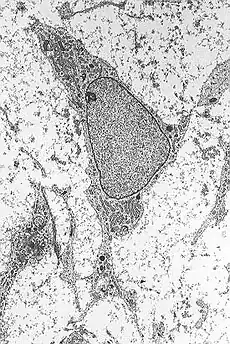

The proposed method includes the conversion of mesenchymal stem cells (cells usually intended for generation of bones and adipose tissue) into neurons after a short exposure to retinoic acid diluted in ethanol.[15] The therapy consists in removing cells from the bone marrow of patients, their in vitro manipulation (incubation of stem cells for 2 hours in an 18 micromolar solution of retinoic acid), and finally their infusion into patients themselves.[16]